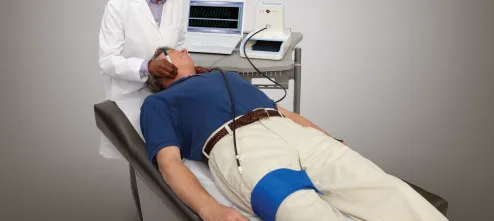

- تست PWV(تست سرعت موج نبض)

- تست ABI